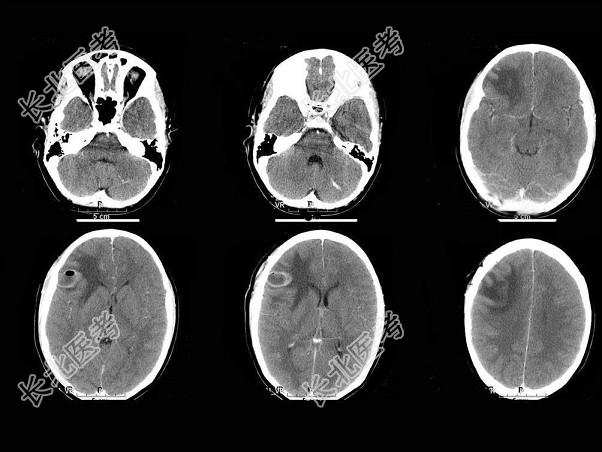

- 单项选择题男,32岁, 发热,头痛, 结合CT图像,最可能的诊断是 ( )

A、星形细胞瘤

B、脑转移瘤

C、脑脓肿

D、脑包虫病

E、脑血肿吸收期